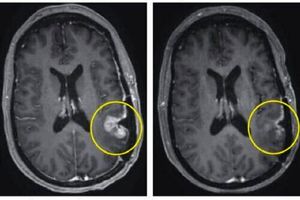

محققان مرکز سرطان عمومی مَس(Mass) در حال اراعه گزارشی از نتایج تحقیقات بر سه بیمار در یک کارآزمایی بالینی درمان CAR-T برای گلیوبلاستوما(GBM) است که یک تومور مغزی با رشد … Read More